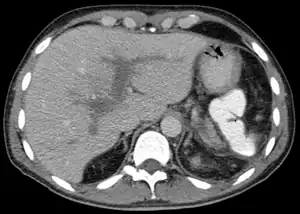

Portal vein thrombosis on computed tomography (left) and cavernous transformation of the portal vein after 1 year

The diagnosis of portal vein thrombosis is usually made with imaging confirming a clot in the portal vein; ultrasound is the least invasive method and the addition of Doppler technique shows a filling defect in blood flow. PVT may be classified as either occlusive or nonocclusive based on evidence of blood flow around the clot.[5] An alternative characterization based on site can be made: Type 1 is limited to the main portal vein, Type 2 involves only a portal vein branch (2a, or 2b if both branches are affected), and Type 3 if clot is found throughout both areas.[8] Determination of condition severity may be derived via computed tomography (CT) with contrast, magnetic resonance imaging (MRI), or MR angiography (MRA). Those with chronic PVT may undergo upper endoscopy (esophagogastroduodenoscopy, EGD) to evaluate the presence of concurrent dilated veins (varices) in the stomach or esophagus.[3] Other than perhaps slightly elevated transaminases, laboratory tests to evaluate liver function are typically normal.[1] D-dimer levels in the blood may be elevated as a result of fibrin breakdown.